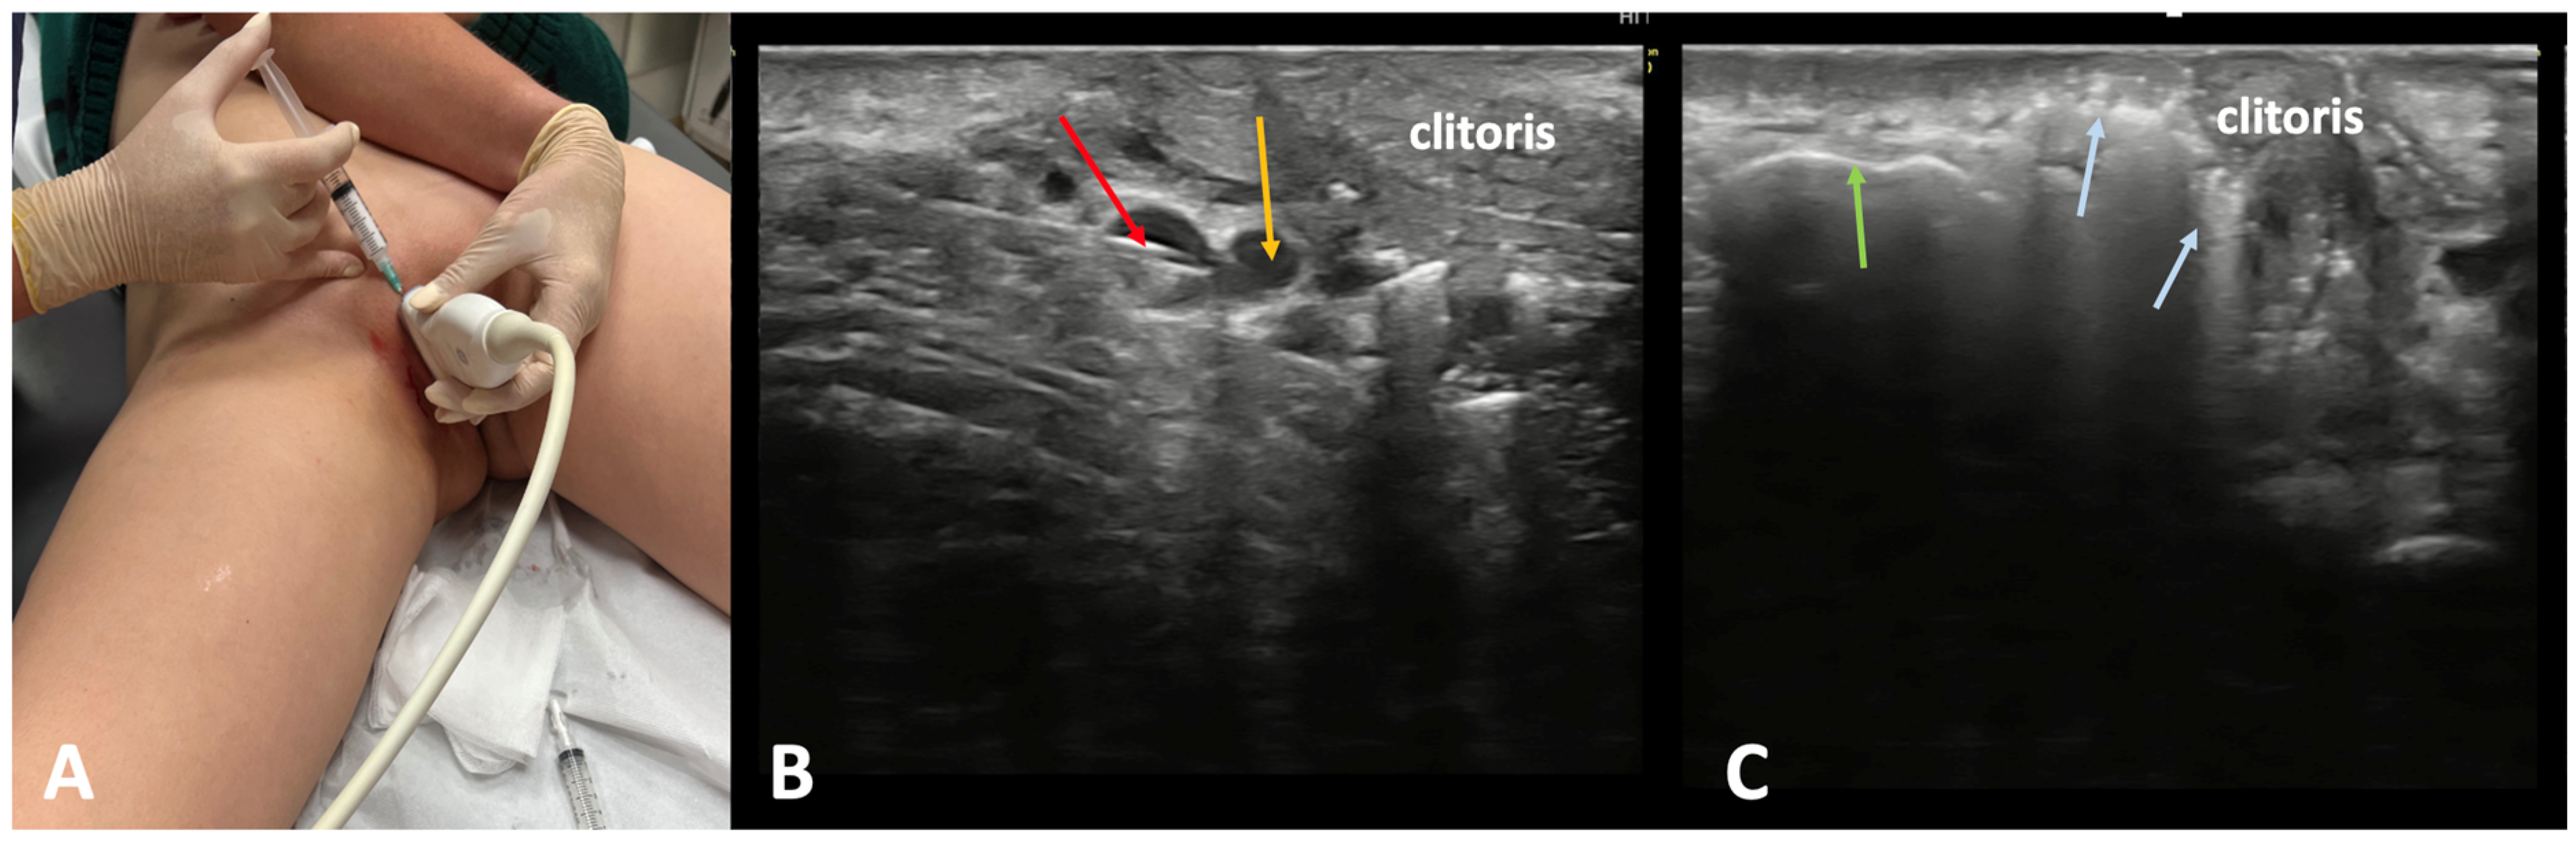

3.1. Treatment of Patients Without Pelvic Symptoms

3.2. Treatment of Patients with Pelvic Symptoms